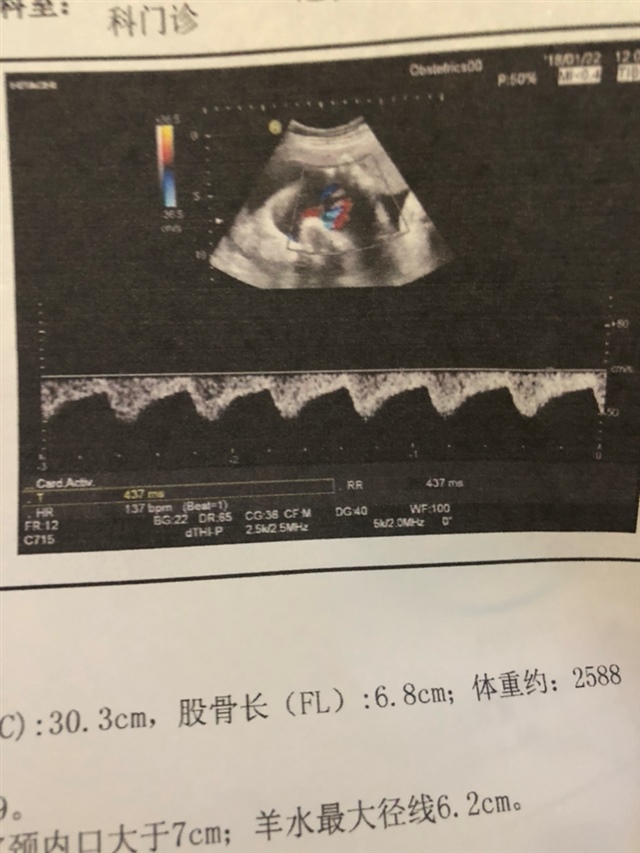

蛮夫人:据说男孩头大腿短,双顶径减股骨长大于二是男孩,小于二是女孩,还有你这胎心率低于150,男孩几率大些。不知道准不准,别当真